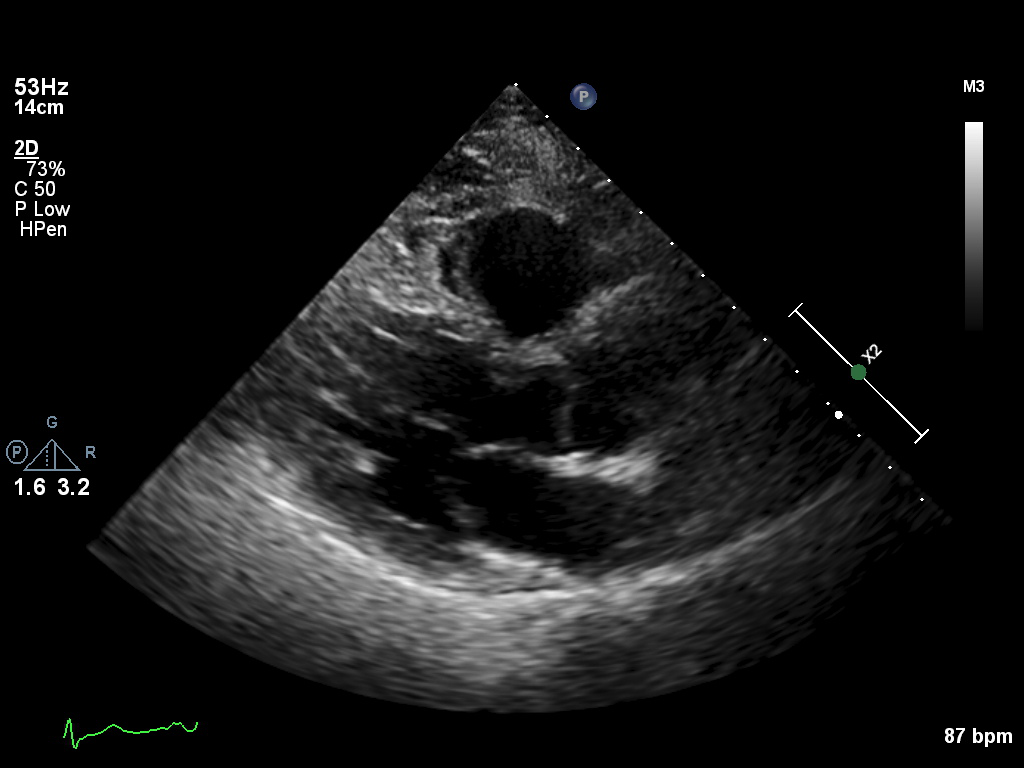

ImageView NameDescription

a2ch-full a2ch-full Apical 2-chamber, covering the depth of the whole of the LV and LA

a2ch-la a2ch-la A2CH with Doppler near MV/LA or 2D not covering full LV depth

a2ch-lv a2ch-lv A2CH covering the whole depth of the LV, but not the whole depth of the LA

a3ch-full a3ch-full Apical 3-chamber, covering the whole depth of the LV and the LA

a3ch-la a3ch-la A3CH with Doppler near MV/LA or 2D not covering full LV

a3ch-lv a3ch-lv A3CH covering the whole depth of the LV, but not the whole depth of the LA

a3ch-outflow a3ch-outflow A3CH emphasizing LVOT (colour focused on LVOT or limited b&w of LVOT area)

a4ch-full a4ch-full Apical 4-chamber showing the full depth of all four chambers (no LV/RV focus)

a4ch-ias a4ch-ias Apical 4-chamber, focused on the inter-atrial septum

a4ch-la a4ch-la A4CH with Doppler near MV/LA or 2D covering full LA, not full LV

a4ch-lv a4ch-lv A4CH covering the whole depth of the LV, not the whole depth of the LA

a4ch-ra a4ch-ra Apical 4-chamber focused on the right atrium, or colour Doppler on TV/RA

a4ch-rv a4ch-rv Apical 4-chamber focused on the right ventricle

a5ch-full a5ch-full Apical 5-chamber from apex to back of the atria, no LVOT colour

a5ch-outflow a5ch-outflow A5CH including LVOT; may lack full depth or has LVOT colour

apex apex Any apical window whose depth is insufficient to reach the mitral ring